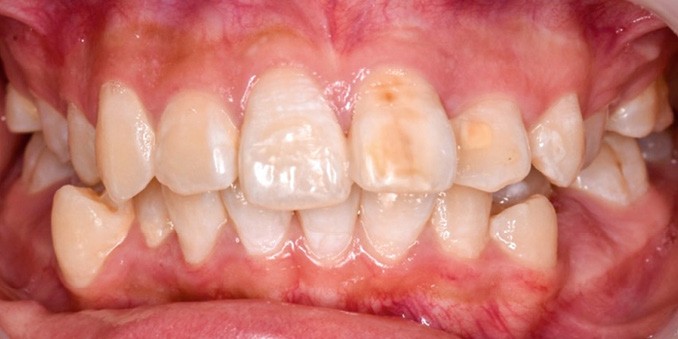

Une patiente âgée de 12 ans se présente en consultation, motivée par la position de son incisive centrale maxillaire, décrite comme « en avant », marquée par une dyschromie et une mobilité de grade 2 selon Muhlemann. L’examen clinique montre l’absence de 23 sur l’arcade, une dysharmonie dents-arcade marquée, un surplomb accentué, et une déviation des milieux inter-incisifs, conséquence du comblement spontané de l’espace de 23. L’ensemble s’inscrit dans un contexte de Classe I d’Angle molaire. L’orthopantomogramme révèle l’inclusion de 23, associée à une résorption radiculaire étendue aux deux tiers de 21. La 22 ne présente aucune altération visible.

La patiente, de profil normodivergent, présente une Classe I squelettique sans troubles fonctionnels (fig. 1-8).

Par ailleurs, le rendu esthétique final du sourire reste marqué par une légère dyschromie entre les 11 et 21. Cela s’explique à la fois par la teinte plus saturée de la canine stratifiée, mais aussi par la discrète fluorose — visible en début de traitement sous forme de stries blanchâtres sur les incisives maxillaires et mandibulaires. De plus, l’apparition de white spot lesions secondaires au traitement a accentué le contraste chromatique. Un apport de vernis fluoré et une prise en charge par érosion-infiltration des lésions fluorotiques sont prévus afin d’harmoniser les teintes [4].